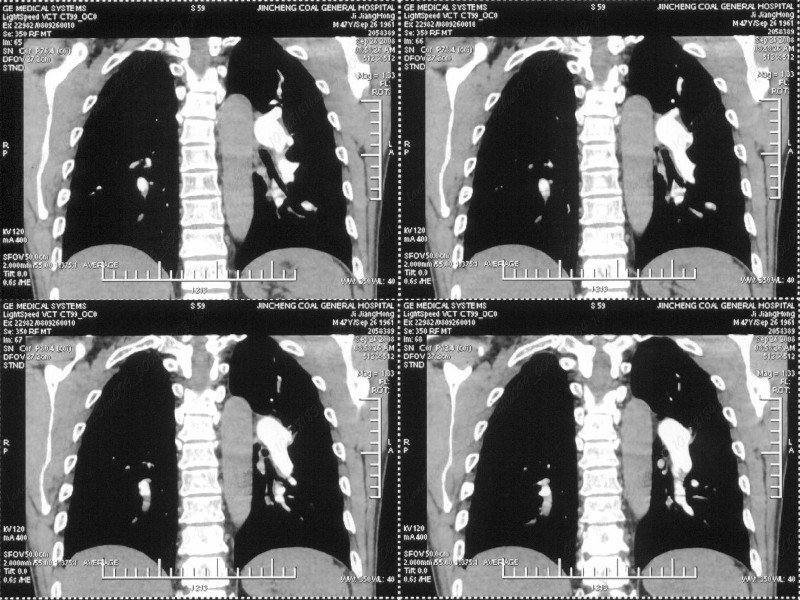

男性,47岁。胸部不适一年,ct检查发现右胸膜下结节。http://www.radida.com/bbs/forum.php?mod=viewthread&tid=46094

右下肺前胸膜下小结节,强化不明显。建议定期观察!

结节未见明显强化,局部胸膜增后粘连,内缘纹理影增重伴小围星灶,局部胸膜下小三角状实变影,尖端见纤维索牵扯征,综合考虑炎性病变,有增殖表现,不出外tb灶

右前胸膜下小结节,边缘有小纤维条索影与胸膜粘连,考虑如炎性假瘤之类慢性病变可能。期待二周后的结果。

右下肺胸膜下小结节,强化不明显。建议定期观察!

右肺静脉充盈缺损,左心房体积小,右肺动脉远端动脉充盈缺损,右肺血管影细小,考虑;右肺动脉远端栓塞.